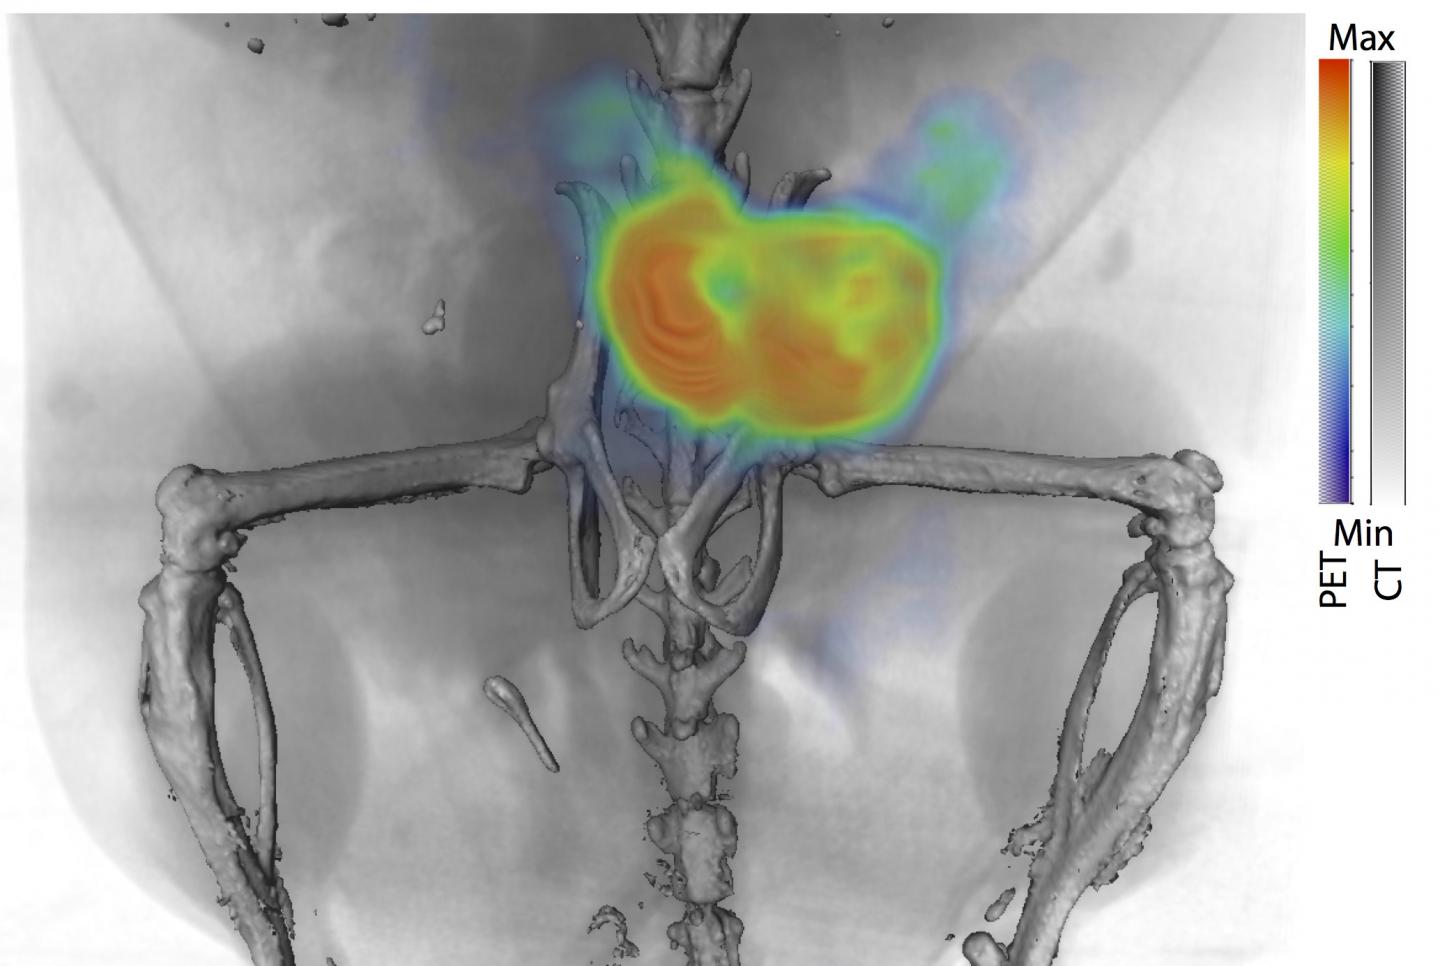

In the next phase of their experiments, the team made 11B6 "light up" during PET and fluorescence imaging by binding it to zirconium-89, creating a traceable radiochemical compound called 89Zr-11B6.

By imaging the 89Zr-11B6 using PET, the team showed that binding 11B6 to hK2 can measure activity of cancerous lesions robustly, in both soft tissue and bone. Prostate and breast cancer often metastasize to bone, therefore detection of lesions in all areas of the body is critical.

To further demonstrate the potential value of 89Zr-11B6 imaging, the team tested the imaging agent in disease models under standard treatment regimens. In one such case, disease activity was imaged and quantified in mice treated with saline and a second group with enzalutamide, a drug used to treat prostate cancer by inhibiting the androgen receptor hormone activity. All of the mice had prostate cancer.

Following initial castration, imaging of 89Zr-11B6 allowed the research team to see lower androgen receptor pathway activity, as one might expect. This effect was augmented in the animals with adjuvant enzalutamide treatment. This may inform current clinical practice as the use of adjuvant enzalutamide after castration may show benefit to patients with prostate cancer.